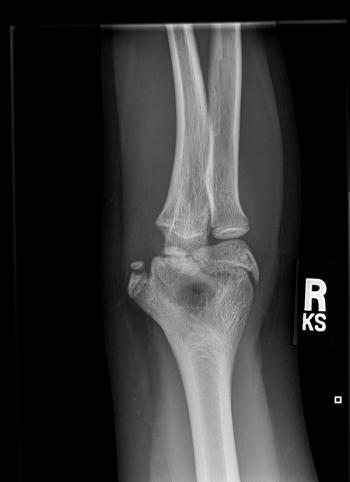

A 12-year-old boy presents to the emergency department with acute pain in the medial aspect of his right elbow after pitching in a baseball game.